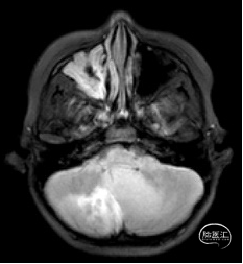

术前MRI

现病史:患者18个月前无明显诱因出现间断头痛,休息后可缓解,开始未予重视,未行特殊治疗。1周前患者无明显诱因出现恶心、呕吐,就诊于当地医院,行颅脑MRI提示:小脑囊实性占位性病变,首先考虑毛细胞星型细胞瘤。现患者为求进一步治疗就诊于我院,门诊以“脑肿瘤”收入院。患者自发病以来神志清,精神可,饮食睡眠正常,二便如常,体重未见明显下降。

小脑肿瘤(毛细胞型星形细胞瘤?)